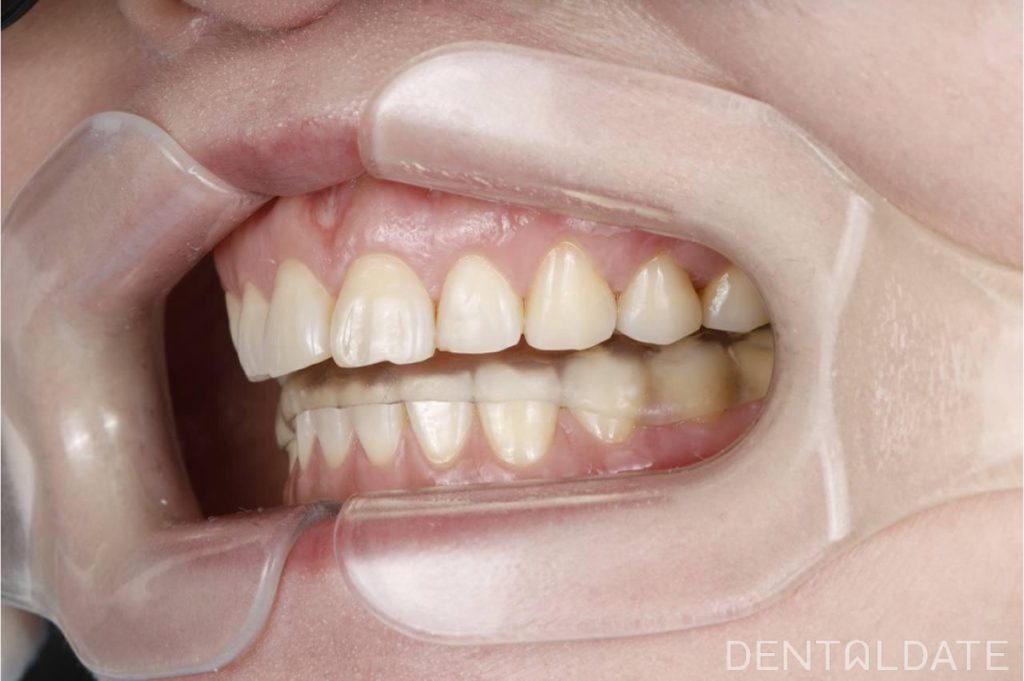

Complex treatment of TMJ arthrosis with orthodontic correction

In this clinical case, we want to demonstrate an approach focused on optimizing treatment timelines for temporomandibular joint (TMJ) osteoarthritis. The patient was diagnosed with TMJ osteoarthritis, confirmed by condylography and CT imaging.

To make the most of the adaptation phase, we simultaneously initiated orthodontic correction of the upper jaw. This approach allows us to significantly shorten the overall treatment time and achieve faster, more effective results.